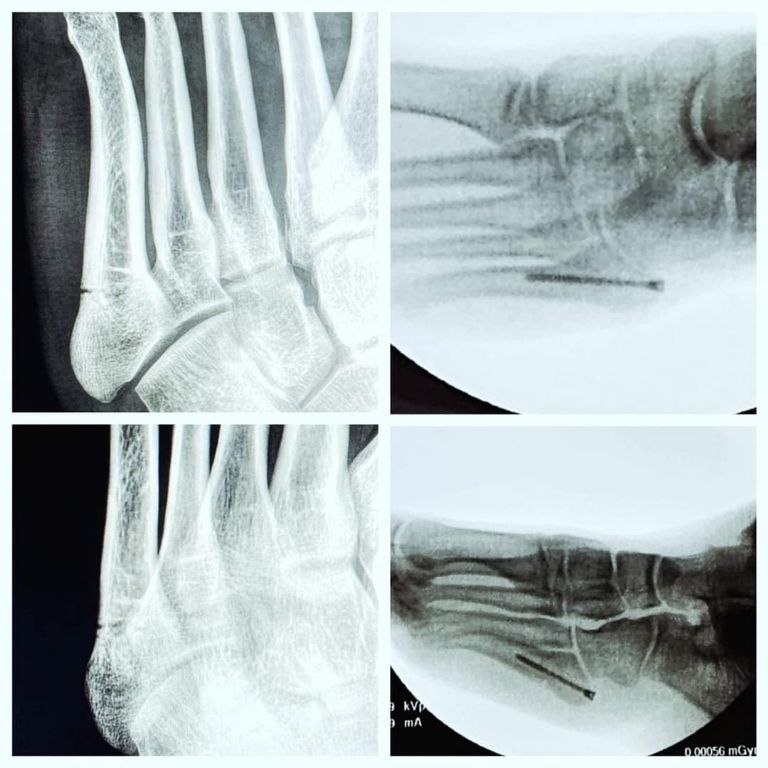

Luego de fracturarse el quinto metatarsiano de lado izquierdo durante el encuentro entre León y Cruz Azul, Fidel Ambriz fue intervenido quirúrgicamente y satisfactoriamente por lo que ha comenzado su etapa de recuperación.

Se trata de un periodo aproximado de seis semanas de recuperación las que vivirá el futbolista nativo de León Guanajuato, por lo que esta fase ha comenzado y en la que será necesario el reposo total en la fase inicial.

¿Qué es la fractura en el quinto metatarsiano?

Se trata fractura en la parte del quinto hueso metatarsiano que está más cerca de la base se llama fractura de Jones. Esta zona del hueso tiene bajo flujo sanguíneo. Esto hace que la sanación sea difícil. Una fractura por avulsión ocurre cuando un tendón desprende un fragmento óseo del resto del hueso.